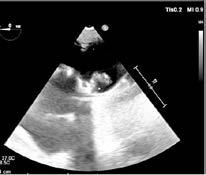

Mujer de 73 años con antecedentes de hipertensión arterial, trombopenia en contexto de lupus eritematoso sistémico, episodio de hipotiroidismo inducido por amiodarona y fibrilación auricular (FA) en estrategia de control de frecuencia cardiaca, anticoagulada con antivitamina K. Como fundamental antecedente cardiológicos destaca una valvulopatía reumática con afectación mitral, que inicialmente se reparó en 1997 mediante abordaje transapical (dejando como secuela aneurisma apical) y se recambió en 2007 por prótesis mecánica. Posteriormente, fue diagnosticada de doble lesión aórtica reumática con estenosis severa e insuficiencia ligera, con fracción de eyección preservada, pero insuficiencia tricuspídea severa e hipertensión pulmonar de predominio poscapilar. Ingresó programada para implante percutáneo de válvula aórtica (TAVI) vía transfemoral, con los principales condicionantes de bloqueo de rama derecha y altura límite de tronco coronario izquierdo (TCI), por lo que se administró clopidogrel 600 mg previamente al procedimiento.

Previo implante de marcapasos temporal yugular derecho se llevó a cabo el procedimiento. Durante la liberación de prótesis mediante inflado del balón, tuvo lugar la embolización supra-anular de la misma, dejando por un lado una insuficiencia aórtica severa y por otro lado ocluyendo parcialmente ambos troncos coronarios. Empleando doble acceso radial se enganchó la prótesis mediante un lazo y se desplazó hacia aorta ascendente, dejando hueco para la colocación de una segunda prótesis en situación correcta y evitando la oclusión de los ostium coronarios y troncos supra-aórticos. En ausencia de bloqueo auriculoventricular se retiró el marcapasos temporal, se evidenció un hematoma yugular derecho y, a través de analítica, se detectó anemización de 2,5 puntos. Mediante angiografía, se descartó enfermedad coronaria y, mediante ecocardiograma transesofágico, se confirmó normoposición de la prótesis, objetivándose al mismo tiempo una disección aórtica.

DIAGNÓSTICO Y ACTITUD INICIAL

Se realizó una tomografía computarizada (TC) con contraste de forma emergente, que mostró una disección aórtica iatrogénica tipo A focal de origen en la zona 0 del cayado con extensión al tronco braquiocefálico derecho (1) sin afectar al resto de troncos supra-aórticos, cayado o aorta descendente (Figuras 1 y 2); además del hematoma

yugular con signos de sangrado activo. La paciente fue trasladada a la unidad de cuidados críticos cardiológicos. Teniendo en cuenta el alto riesgo hemorrágico (necesidad de anticoagulación permanente, administración de clopidogrel previa al TAVR y sangrado activo cervical), el alto riesgo quirúrgico y la ausencia de compromiso neurológico y hemodinámico se optó por manejo conservador (2,3) con monitorización estrecha mediante técnicas de imagen cardiaca y control estricto de la presión arterial (4).

Figuras 1 y 2: Prótesis aórtica migrada y disección aórtica focal tipo A, de origen en la curvatura menor del arco aórtico (zona 0) hasta la bifurcación de la arteria braquiocefálica derecha; sin afectación de del resto de troncos supra-aórticos, del resto del cayado aórtico o de la aorta descendente.